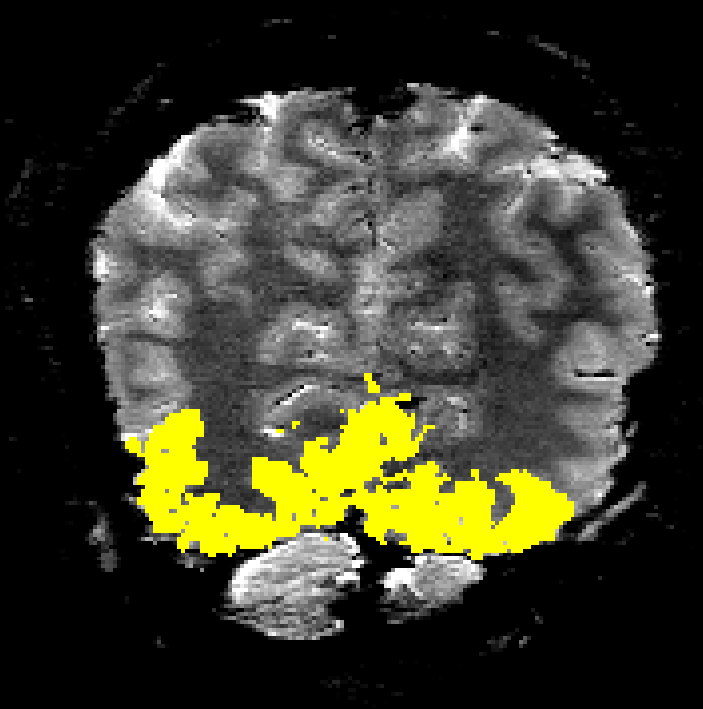

mit_Mask renzohuber July 2, 2018July 2, 2018 Published by renzohuber View all posts by renzohuber Published July 2, 2018July 2, 2018